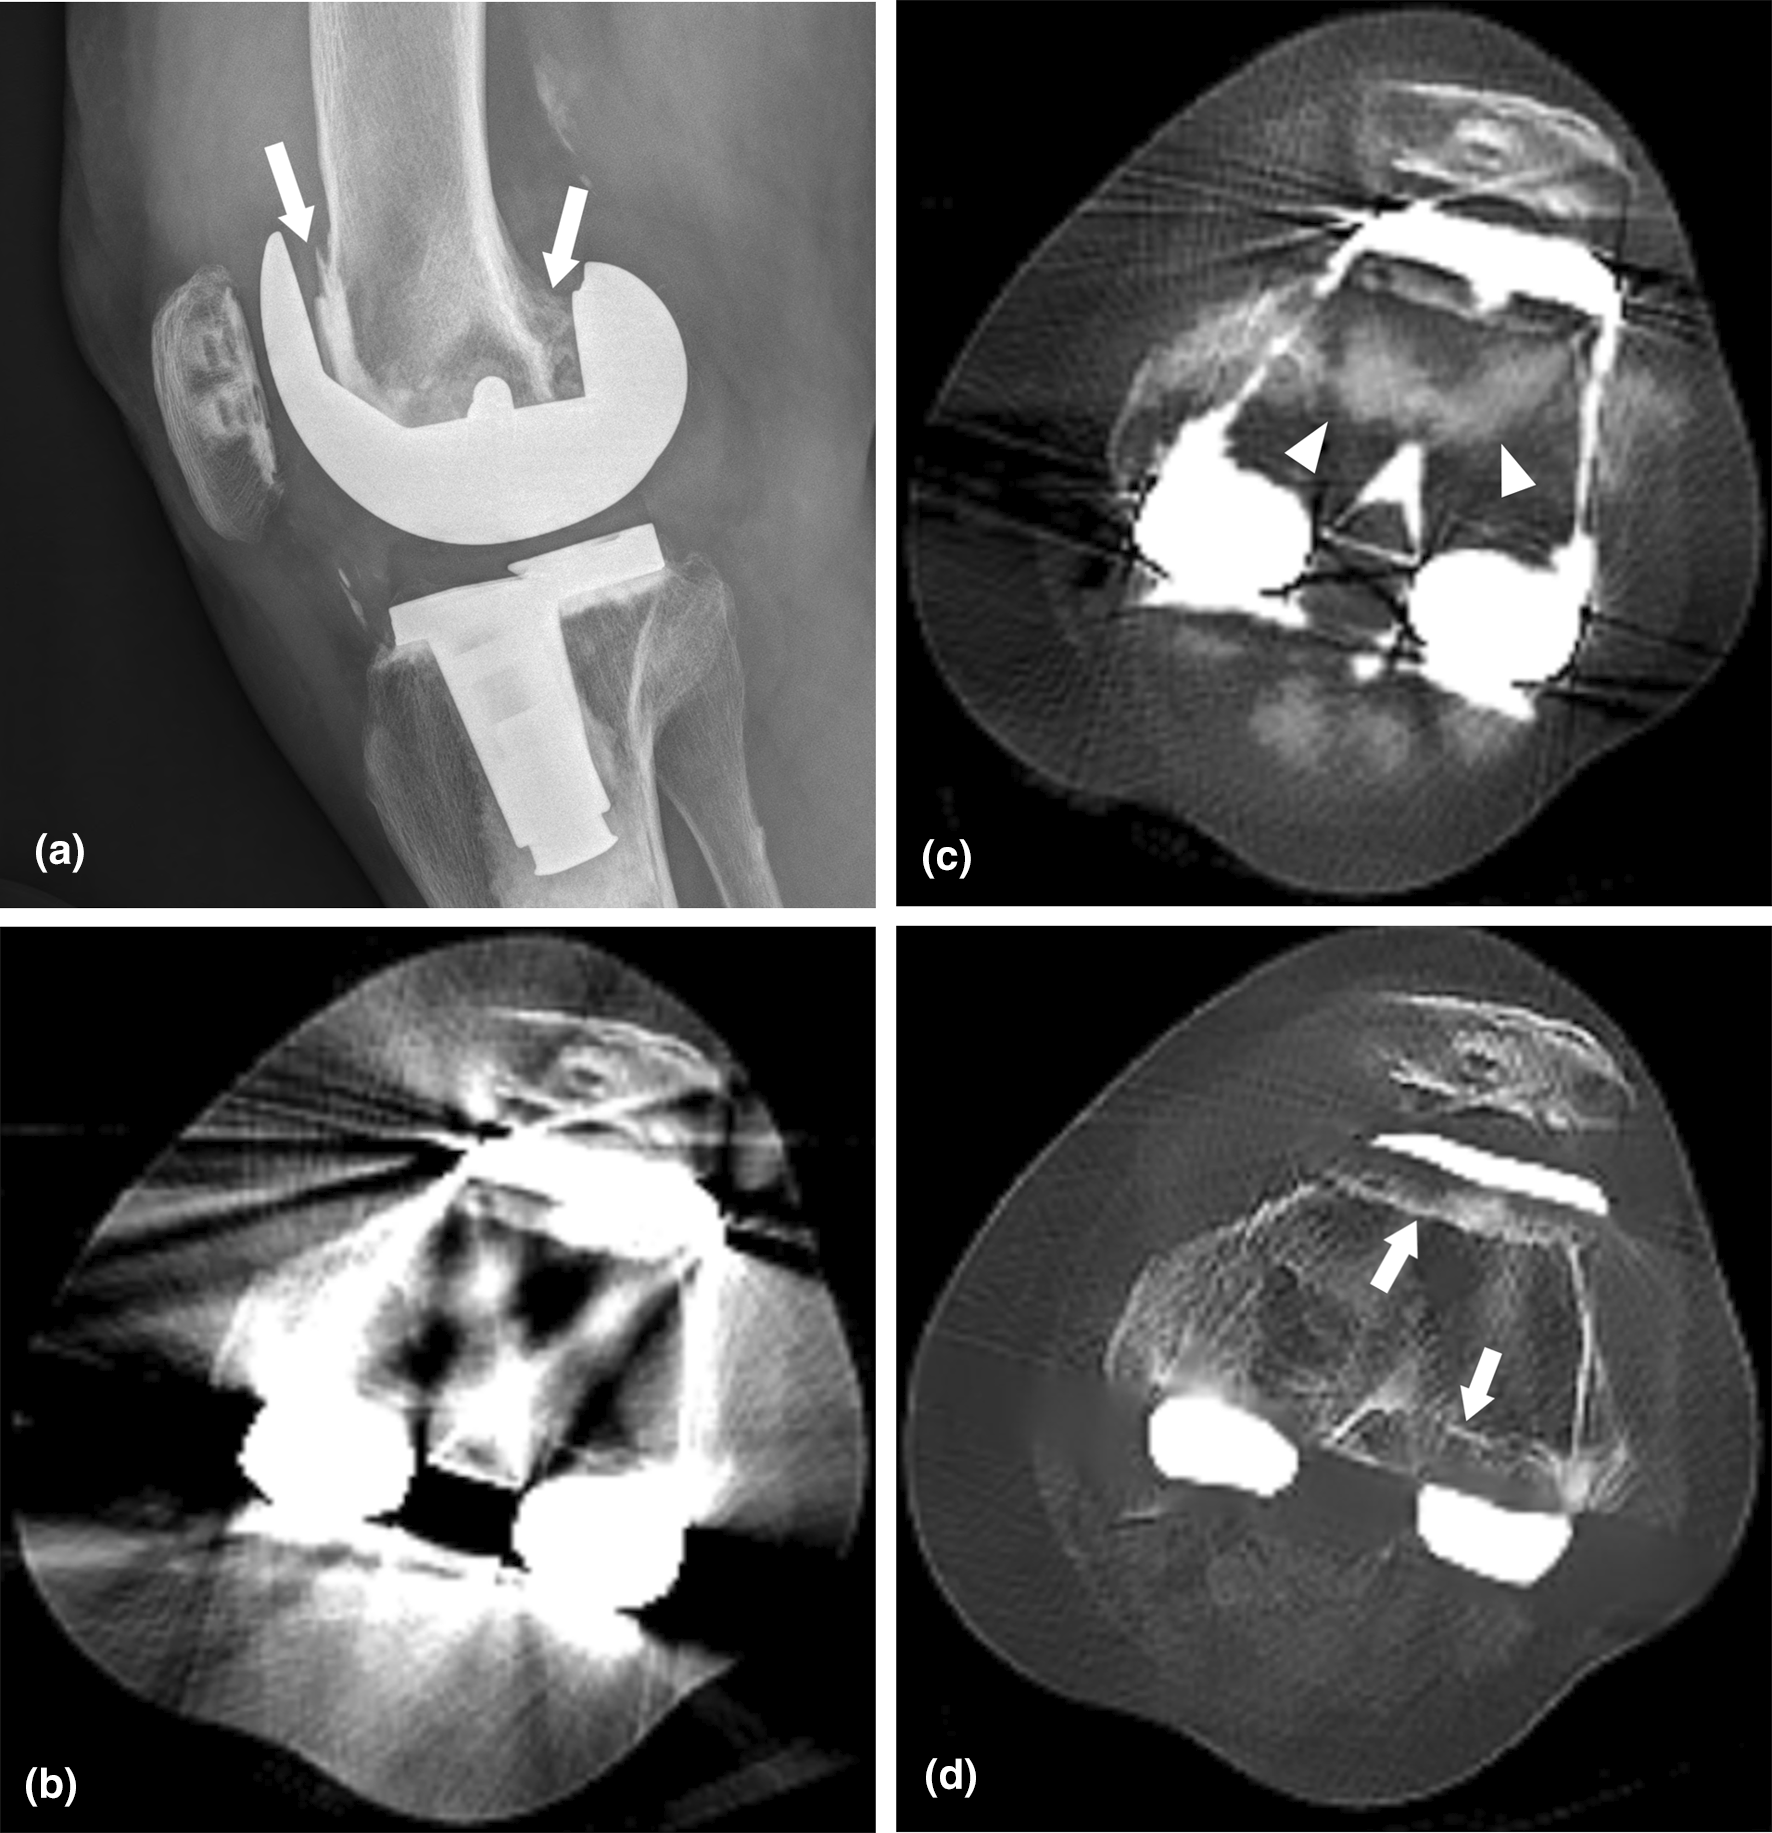

The left knee joint of a 78-year-old woman who underwent revision total knee arthroplasty surgery due to aseptic loosening of the femoral component. (a) A preoperative lateral knee radiograph taken before revision surgery shows radiolucent gaps around the anterior and posterior flanges of the femoral component (long arrows). Axial noncontrast CT images reconstructed with (b) Non-MAR, (c) O-MAR protocol, and (d) KMAR-Net are shown in the bone window setting (window widthā=ā2000 HU, window levelā=ā500 HU). The image of the Non-MAR protocol is of non-diagnostic image quality due to severe streak artifacts. In the O-MAR image, new artifacts of high attenuation that are not visible in the original image interfere with the evaluation of cortical and trabecular bones (arrowhead). KMAR-Net rarely shows these hyperattenuating artifacts while further reducing streak artifacts, and the bone-implant interface gap is more clearly demonstrated (arrows). MAR, metal artifact reduction; O-MAR, metal artifact reduction algorithm for orthopedic implants; KMAR-Net, knee metal artifact reduction network.